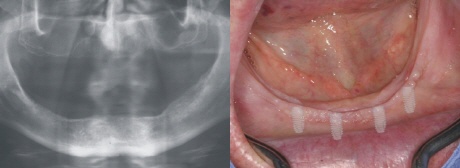

Einheilung

Bei der Variante der Spätversorgung heilen die Implantate im Unterkiefer zwischen zwei bis drei Monaten in den Kieferknochen unbelastet ein, das heiß es werden noch keine Kaukräfte in den Knochen weitergeleitet.

Freilegung

In örtlicher Betäubung werden in einem kleinen Eingriff sogenannte Einheilkappen auf die Implantate geschraubt. Diese Formen nun die Durchtritsstelle der Implantate in der Schleimhaut (Bild oben rechts). Eine Röntgenkontrollaufnahme bestätigt die Einheilung der Implantatschrauben (Bild oben links).